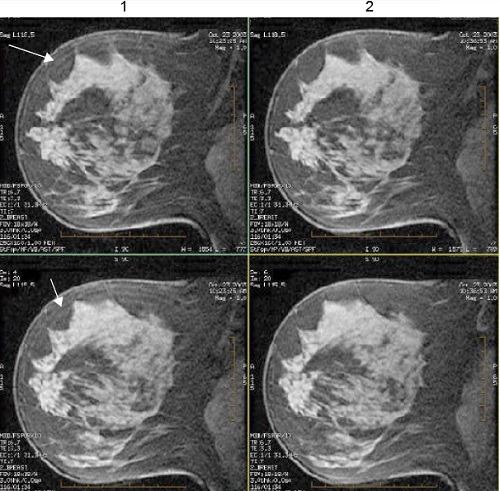

Use the Classic Sequential Ordering User CV with VIBRANT Gradient Echo PSD. The User CV refers to k-space filling technique. The VIBRANT k-space filling technique fills k-space linearly from 1-n and places the center of k-space at exactly half the phase encoding steps. This technique can reduce ring-like image artifacts. There are two options:

| 1 | Classic Sequential Ordering on (note the ring-like artifacts as pointed out by the arrows). |

| 2 | Classic Sequential Ordering off (note the absence of ring-like artifacts). |